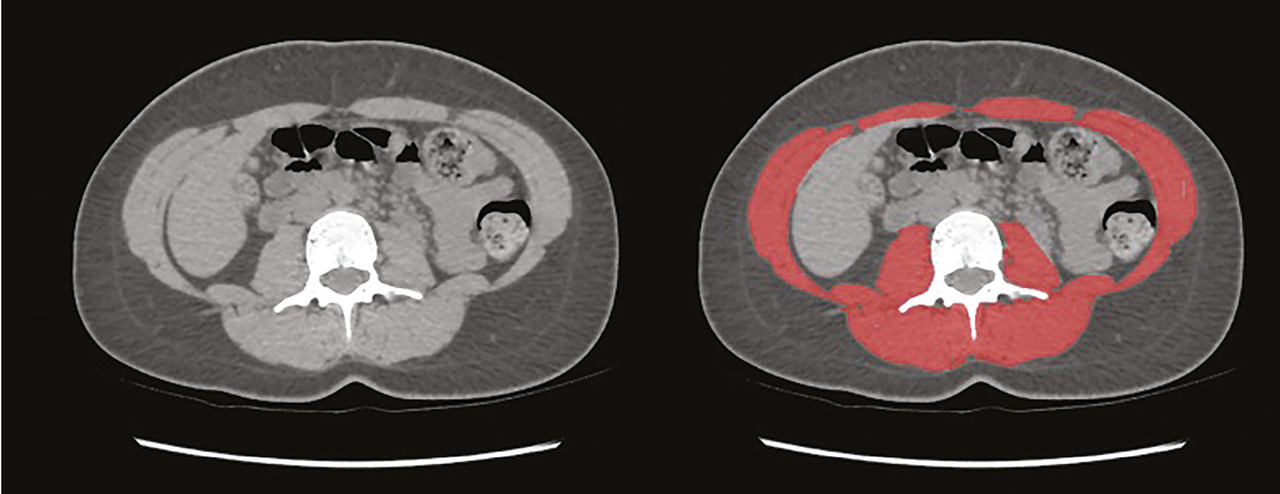

Pour déterminer la surface musculaire en imagerie scanner, deux étapes sont nécessaires.

La première consiste à identifier la troisième vertèbre lombaire puis à choisir une coupe passant par celle-ci (fig. 1).

Sur cette coupe, les muscles sont ensuite identifiés à la fois grâce à leur densité et à leur localisation anatomique, ce qui permet de déterminer la surface musculaire (fig. 2). Comme pour l’indice de masse corporelle, il est recommandé de rapporter la surface musculaire à la taille au carré pour obtenir l’indice de surface musculaire (ISM).